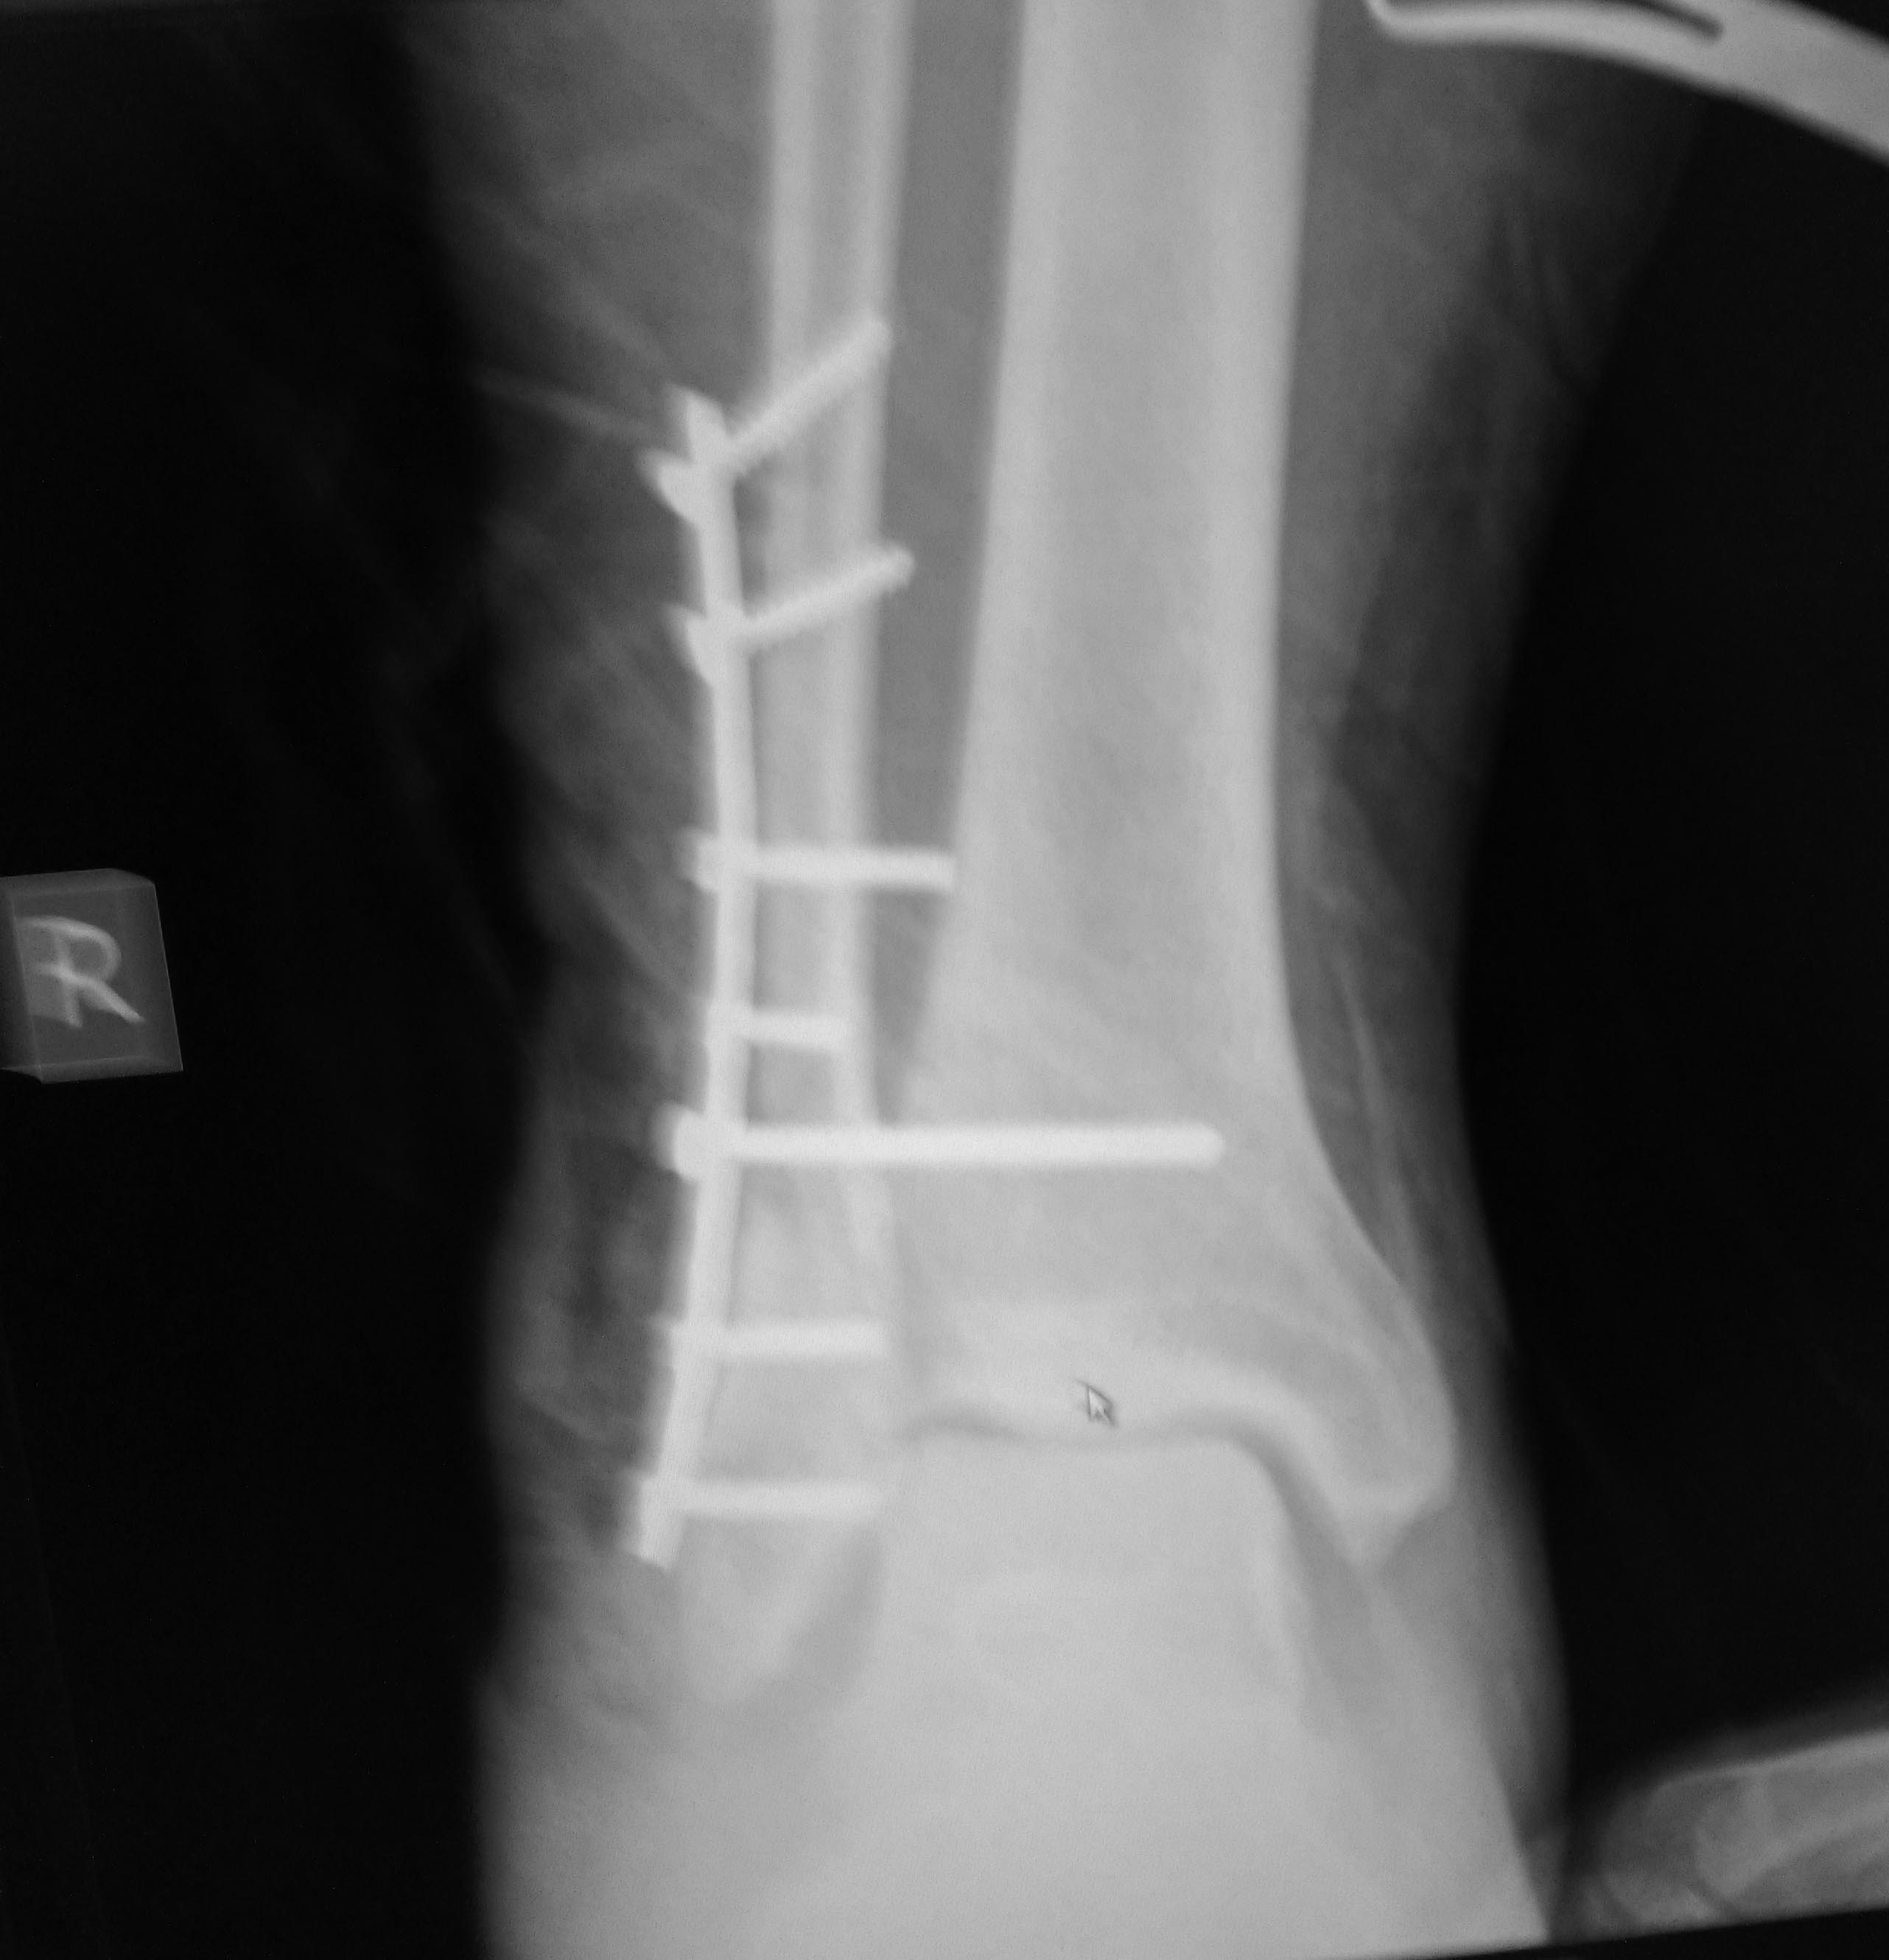

интраоперационно

Перелом несвежий, понимаю. Жаль нет снимка первичного. Не совсем ясен уровень перелома (и его протяженность малоберцовой кости).

Ошибки у Вас интраоперационные -

1 - не восстановлена длина наружной лодыжки, сохраняется укорочение. Поэтому таранная кость смещена латерально и кпереди.

2 - я бы не стал использовать реконструктивную пластину.

3 - Ревизия дельтовидной связки сделана?

Мой вывод - показан реостеосинтез.